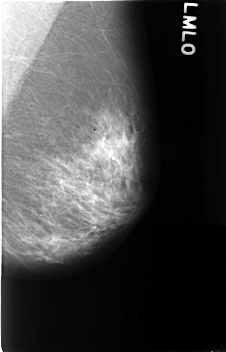

C_0420_1.LEFT_MLO

LEFT_MLO LINES 4568 PIXELS_PER_LINE 2928 BITS_PER_PIXEL 12 RESOLUTION 50 NON_OVERLAY